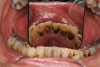

(24.) 68-year-old cancer patient who had complete xerostomia associated with his treatment. SDF attenuated multiple caries lesions. (Photographs courtesy of Dr. Scott Eidson).

Figure 24

(25.) 68-year-old cancer patient who had complete xerostomia associated with his treatment. SDF attenuated multiple caries lesions. (Photographs courtesy of Dr. Scott Eidson).

Figure 25